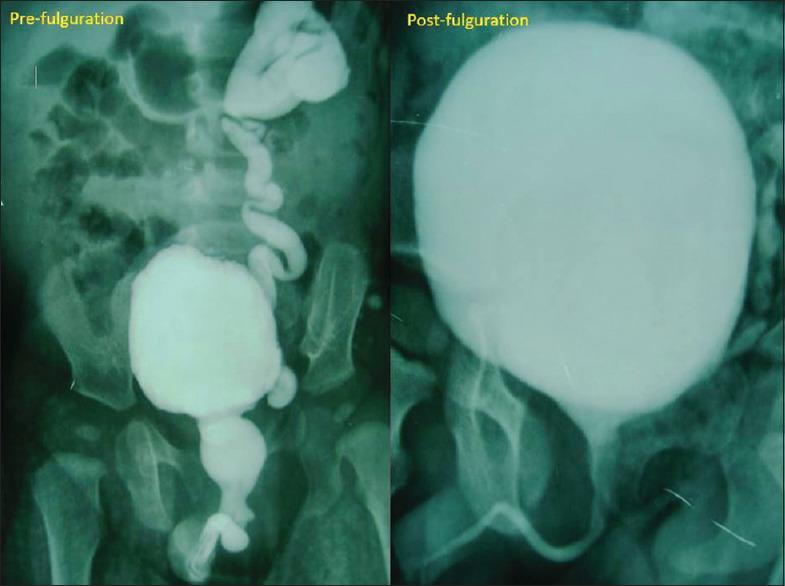

Posterior urethral valves (PUV) is the commonest obstructive uropathy with varied consequences. Though valve fulguration is the treatment of choice, appropriate bladder management modifies outcome and includes rational use of anticholinergics. Here, we aim to evaluate the effects of oxybutynin on the bladder and urinary tract morphology and function. Concurrently, we document adverse effects encountered, patient compliance, and medication adherence.

A retrospective study of children below 5 years of age (2012-2017) post fulguration and on oxybutynin for at least 6 months. Patient demographics, clinical features, renal ultrasound, micturating cystourethrogram, dimercaptosuccinic acid scan, adverse effects, and pill count for medication adherence were collated.

48 children below the age of 5 years were included, and 12 were excluded either due to the presence of concomitant problems or were not on oxybutynin. Of the 36, four were lost to follow-up and one had died due to an unrelated condition. Thus, a total of 31 children were analyzed. At follow-up, 28/31 patients were asymptomatic, two had daytime incontinence, and one had recurrent urinary tract infection. All patients except one have preserved renal function tests. On ultrasonography, hydroureteronephrosis worsened in only 1/25 children and two showed significant post void residues. The resolution of vesicoureteral reflux was noted in almost 50%. 4/31 renal units had progressive scars. Only two parents defaulted medication. Urodynamic study done in half of these children showed stable bladder pressures except in two.

Oxybutynin therapy following adequate valve fulguration aids upper tracts preservation by stabilizing deranged bladder dynamics. The medication is well tolerated with minimal or no side effects.

后尿道瓣膜(PUV)是最常见的梗阻性泌尿系统疾病,后果多样。尽管瓣膜电灼术是首选治疗方法,但适当的膀胱管理可改善预后,其中包括合理使用抗胆碱能药物。在此,我们旨在评估奥昔布宁对膀胱及尿路形态和功能的影响。同时,我们记录所遇到的不良反应、患者依从性和药物依从性。

对2012年至2017年接受电灼术且服用奥昔布宁至少6个月的5岁以下儿童进行回顾性研究。整理患者的人口统计学资料、临床特征、肾脏超声、排尿性膀胱尿道造影、二巯基丁二酸扫描、不良反应以及药物依从性的药丸计数。

纳入48名5岁以下儿童,12名因存在合并问题或未服用奥昔布宁而被排除。在这36名儿童中,4名失访,1名因无关疾病死亡。因此,共分析了31名儿童。随访时,31名患者中有28名无症状,2名有日间尿失禁,1名有复发性尿路感染。除1名患者外,所有患者的肾功能检查均正常。超声检查显示,仅1/25的儿童肾盂输尿管积水加重,2名儿童有明显的残余尿量。近50%的患者膀胱输尿管反流得到缓解。31个肾单位中有4个出现进行性瘢痕。只有2名家长未按时服药。对其中一半儿童进行的尿动力学研究显示,除2名儿童外,膀胱压力稳定。

在充分的瓣膜电灼术后,奥昔布宁治疗有助于通过稳定紊乱的膀胱动力学来保护上尿路。该药物耐受性良好,副作用极小或无副作用。